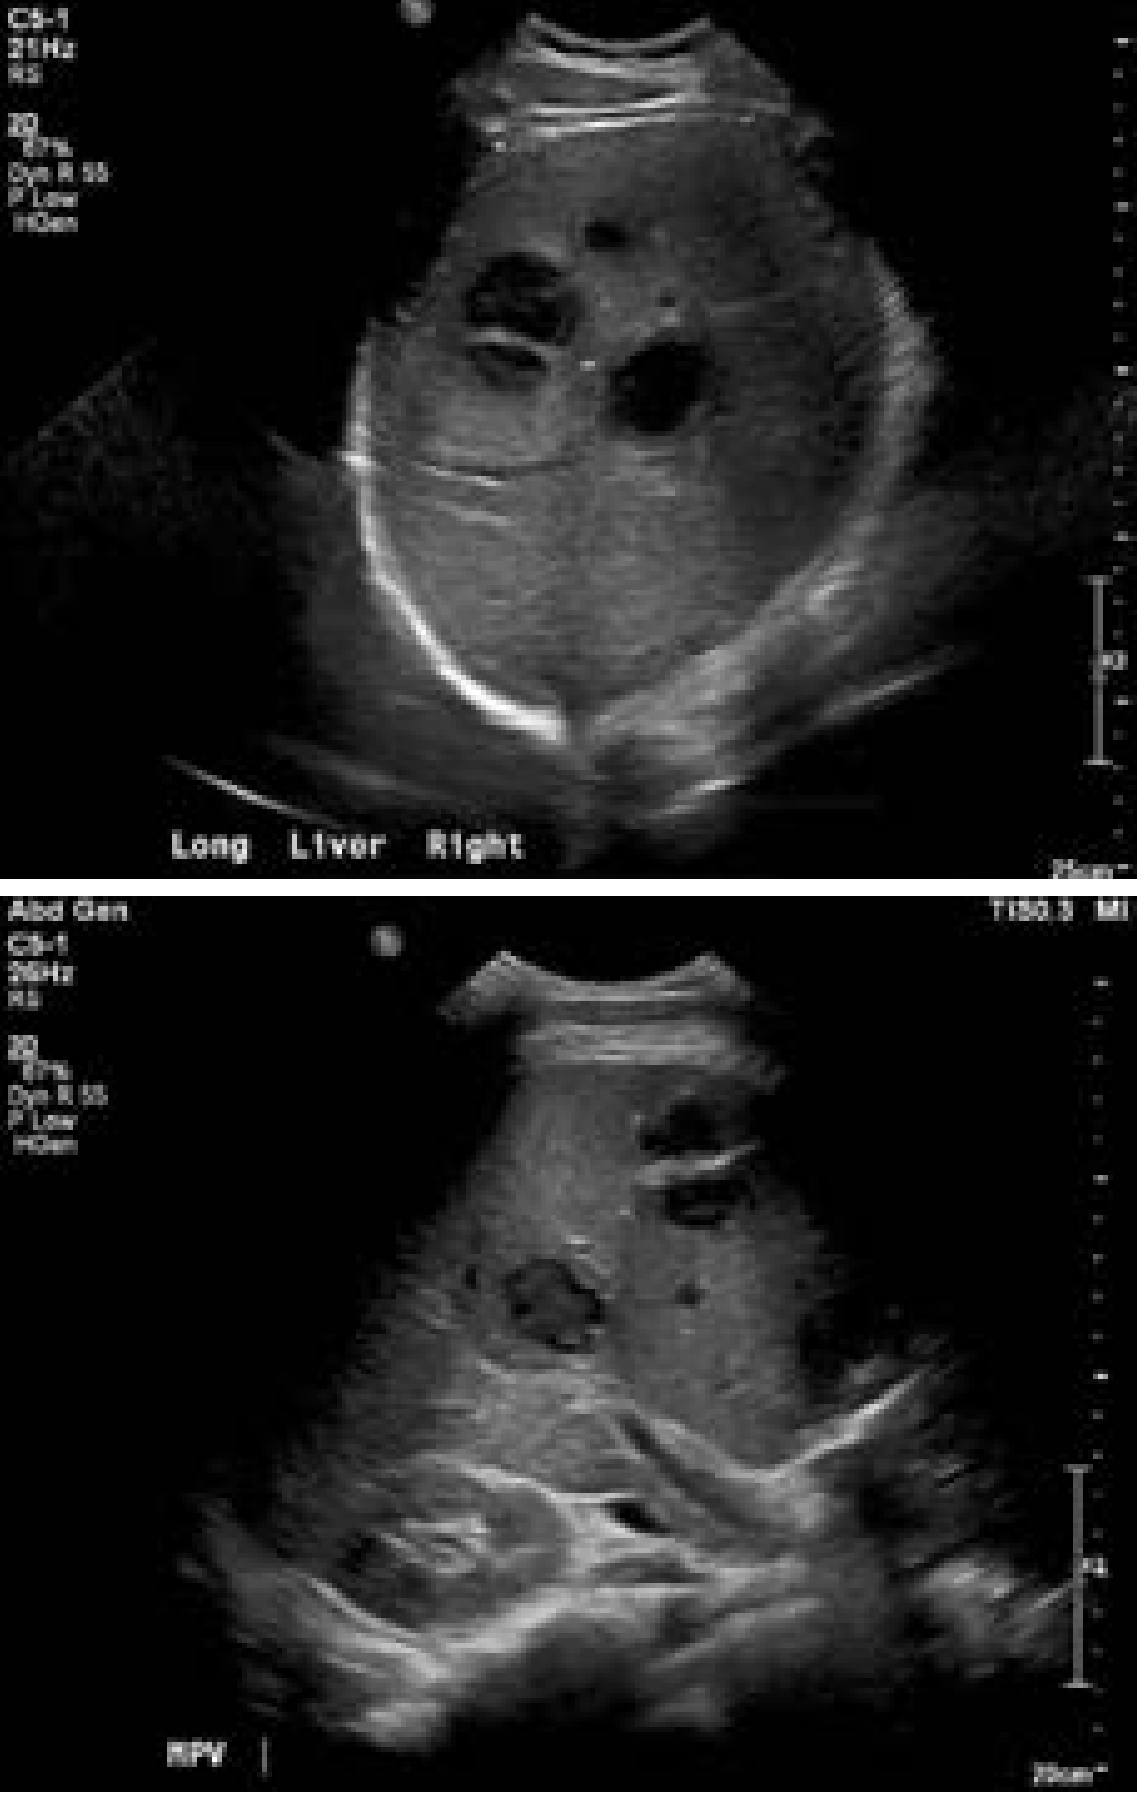

Ultrasound of liver abscess

Ultrasound images of liver abscess